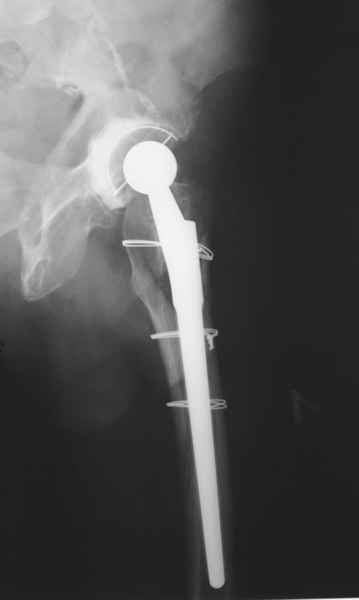

2. Применение ножки дистальной фиксации, мы отдаем предпочтение ножке Вагнера с фиксацией проксимального отдела на ножке. Более травматичное вмешательство, но при стабильной фиксации ножки реабилитация идет в обычном режиме.

Хочется показать два подобных случая, П-ка Зубарева 72 лет и п-т Гладковский 80 лет. Сразу принимаю замечание, что это были ножки цементной фиксации, просто под руками не было бесцементника.